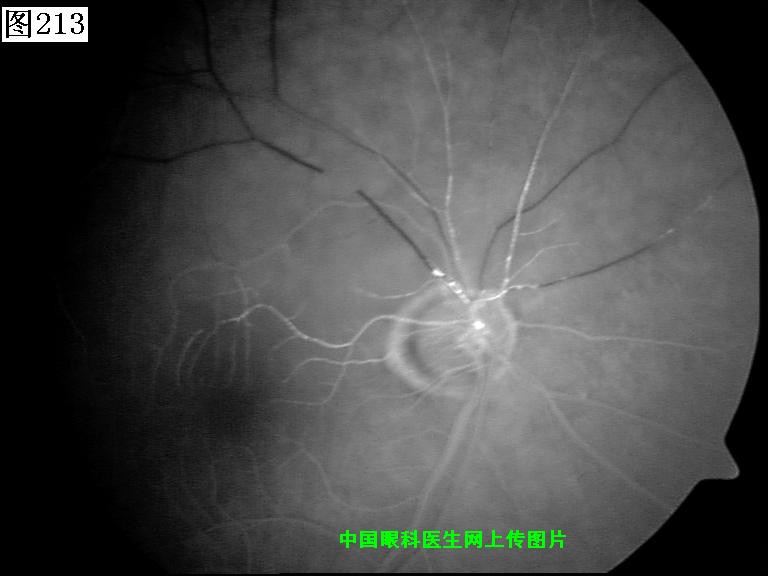

213 214 215 216